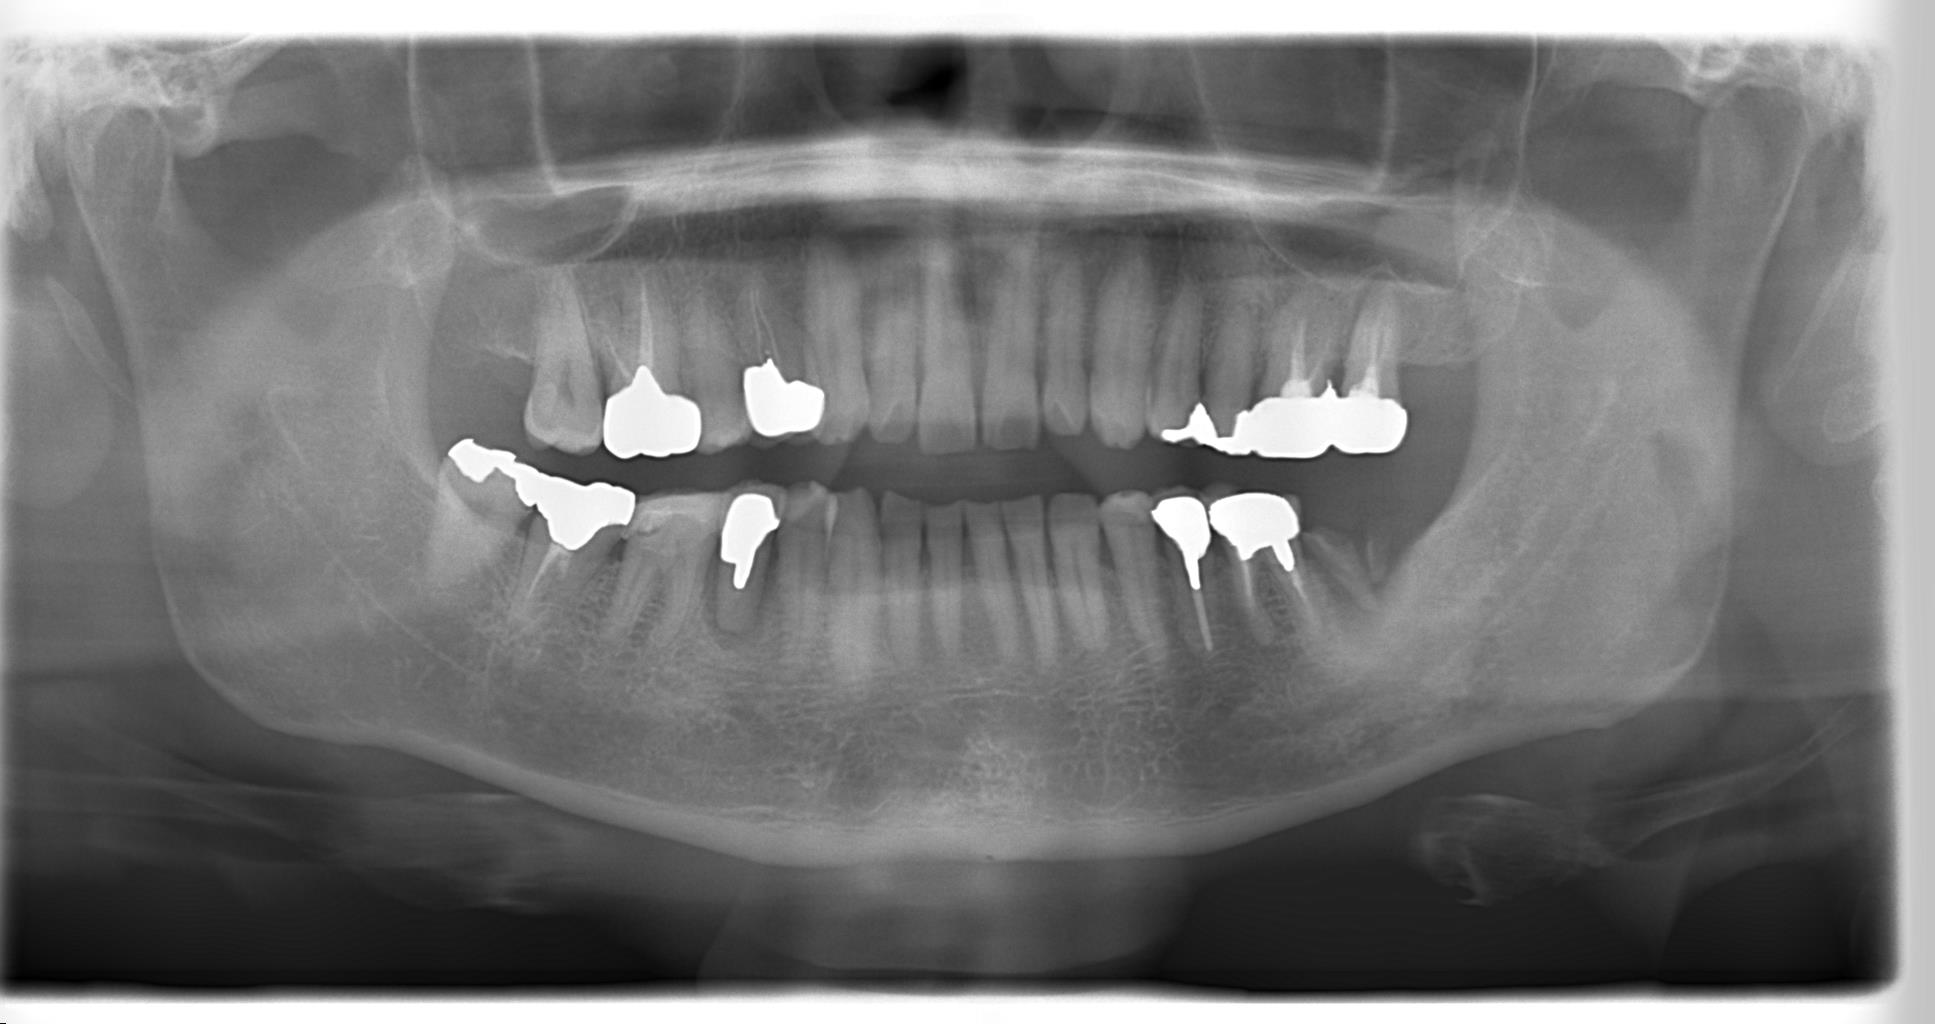

下のレントゲン写真の患者さんは、左下の第2大臼歯(写真では一番右下の歯)が歯根破折しており抜歯を余儀なくされました。

一番後方の歯の欠損ということもあり、インプラントによる治療も考えられますが、患者さんは希望されておりませんでした。

そこで提案させていただいたのが、歯の移植です。

右下(写真では一番左下)だけに親知らずが存在しており、対合歯もなく機能していない状態だったので、これが有効活用できれば、入れ歯を入れたり、歯を削ったりすることなく、最も自然な形で欠損部を改善できます。

早速CT撮影を行い、欠損部の骨の状態と親知らずの形態を確認したところ、移植可能な状態でしたので、患者さんと再度相談させていただき、治療を進めていきました。